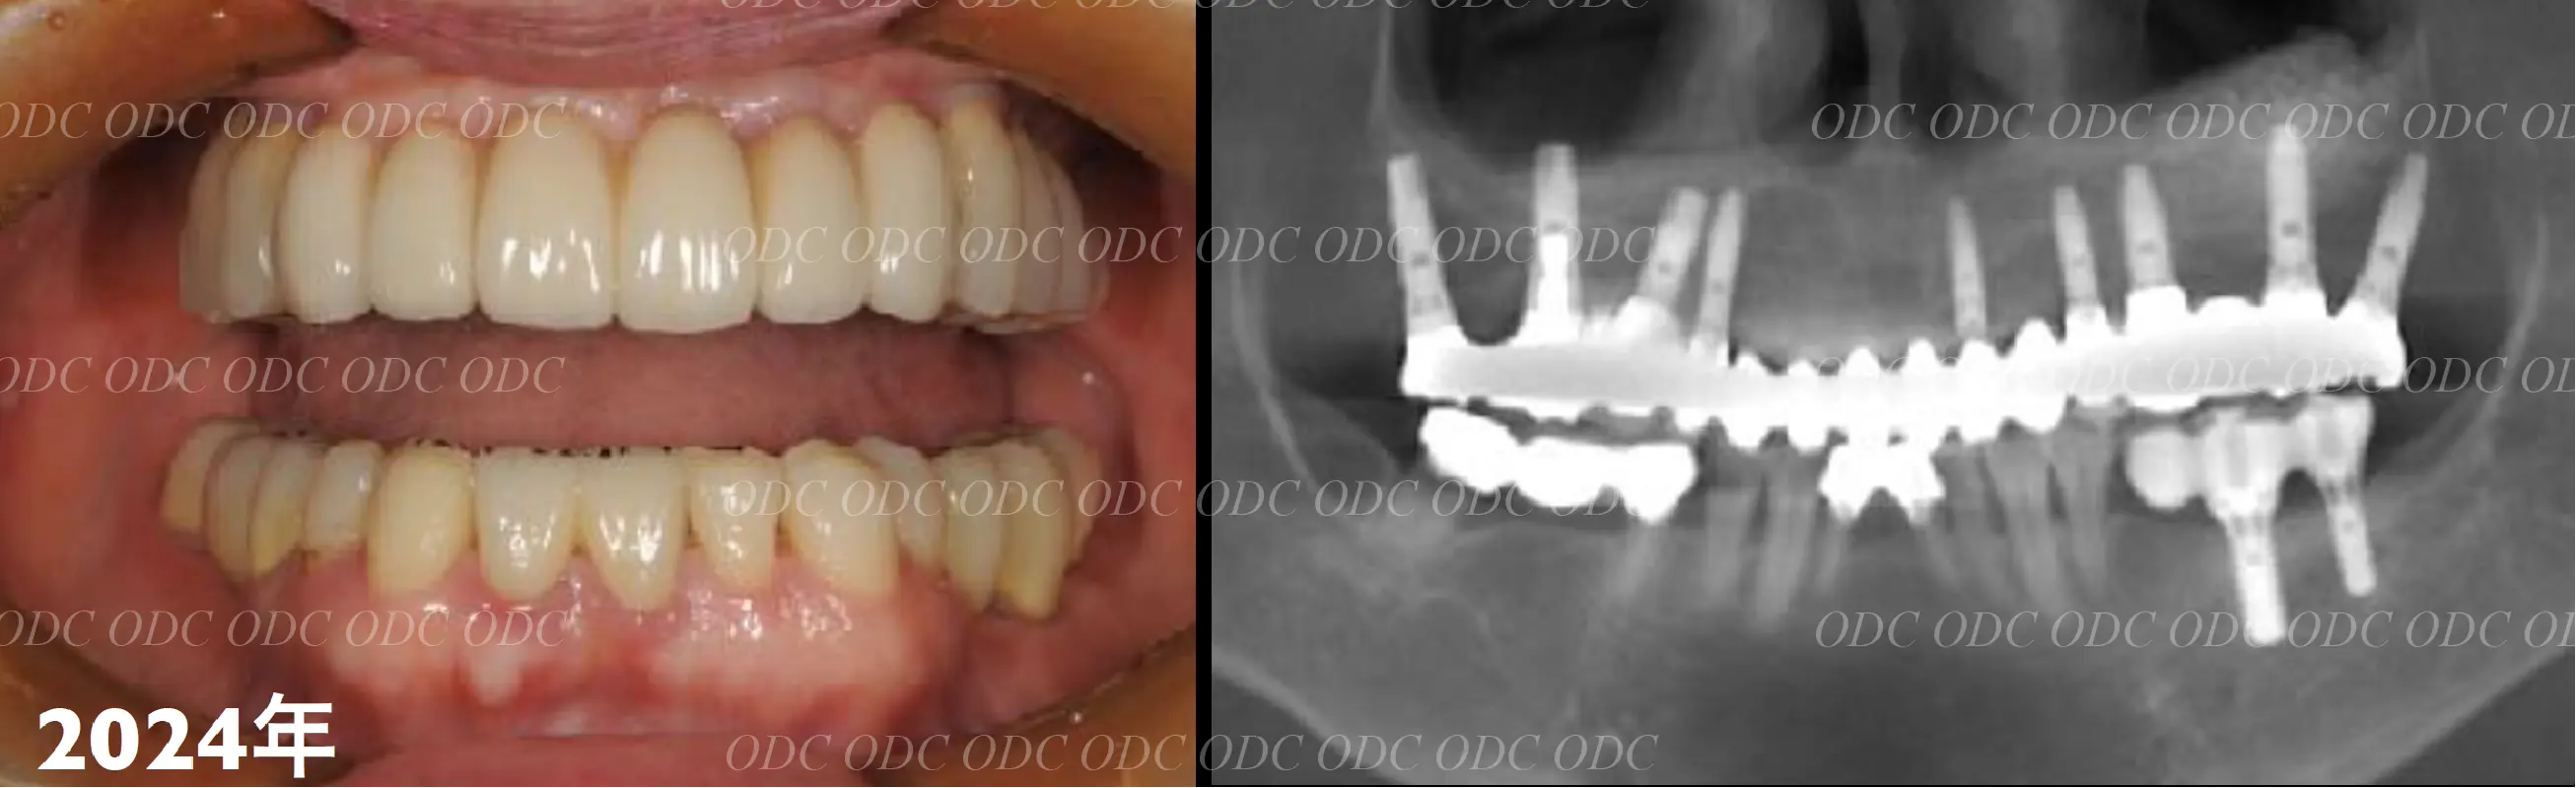

2011年、噛めないという主訴で65歳の男性が来院されました。

全顎的な治療を希望されていましたので、口腔内はもちろん骨格・顔貌・顎関節の診断を行い治療目標を設定致しました。

上顎天然歯に関しては矯正治療、下顎にはフルマウスのインプラント治療を計画致しました。

顎関節の安定を確認した後、矯正治療とインプラント治療を並行して行いました。

約3年の治療期間を経て、計画通りの満足のいく結果を獲得することができました。

2014年、治療終了時の口腔内の状態です。

インプラント上部構造はCADCAMによって作成されたジルコニアの上部構造です。

2024年、治療終了後約10年が経過いたしました。

顎関節を考慮した包括的な治療を行うことで咬合状態(噛み合わせ)は現在もとても安定した状態です。